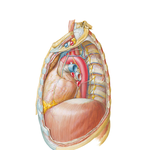

• Mediastinum: Right Lateral View

234. Mediastinum: Right Lateral View